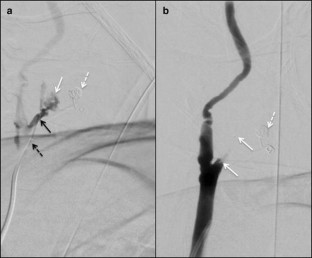

Fig. 2